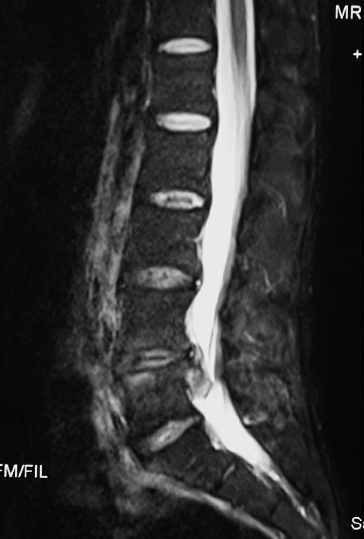

CT显示L4/5节段的椎间盘突出脱垂型(图1)。MRI示L4/5节段的椎间盘突出到Ⅲ层面(图2)。红外热成像显示左侧下肢的皮温明显低于右侧(图3)。

图2 MRI L4~5节段矢状位片:椎间盘脱垂到Ⅲ层面